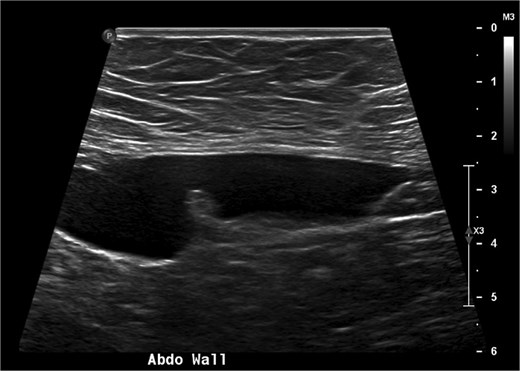

A 38-year-old woman presented to clinic with chronic supraumbilical abdominal pain. This was not associated with any gastrointestinal or constitutional symptoms, or systemic unwellness. She did not have any significant medical history. She had a Caesarean section 5 years prior. On examination, a large mass was palpated in the supraumbilical area; there was a small reducible fat-containing umbilical hernia, and there were no signs of peritonism. Blood tests including serum tumour markers were unremarkable. Computed tomography (CT) of the abdomen revealed an 8 × 3 cm hypodense lesion just deep to the anterior abdominal wall (Fig. 1). An ultrasound (USS) characterised this lesion as an 8 × 7 × 3 cm cyst with simple internal contents suggestive of a falciform ligament cyst (Fig. 2).

Axial (a) and coronal (b) CT images showing the 8 cm falciform ligament cyst (arrows) just deep to the anterior abdominal wall.